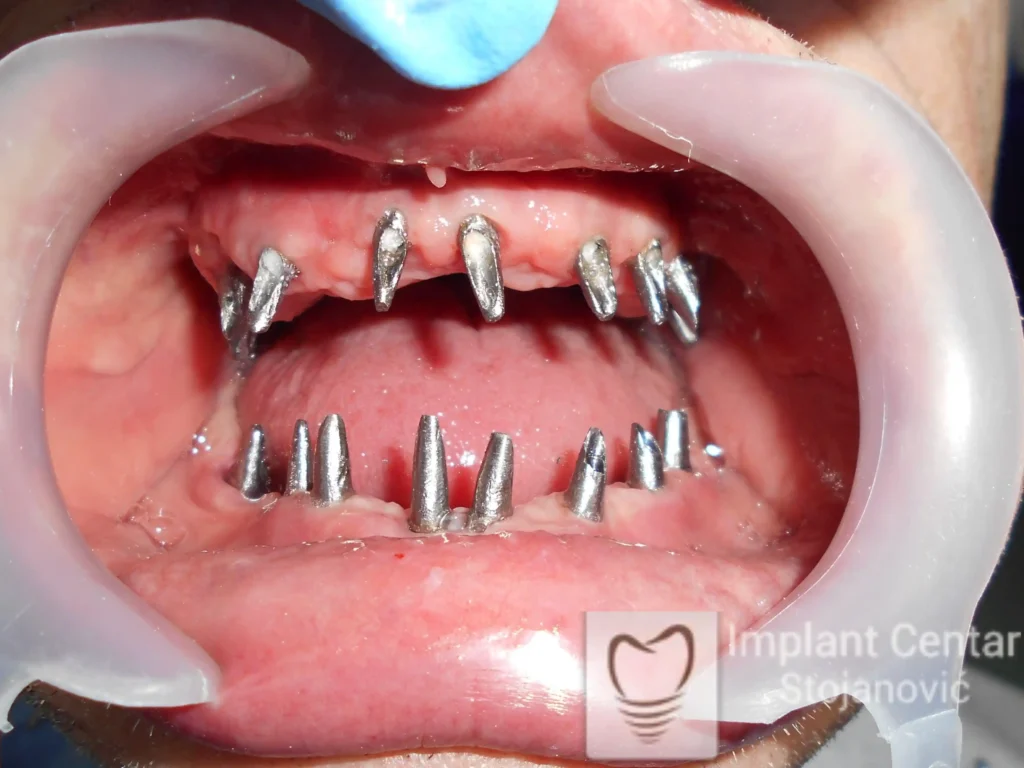

Na slici 1. i slici 2. prikazan je izgled pacijenta pre početka terapije – klinički i rendgenološki.

Nakon vađenja zuba, ugrađeni su implantati. Na slici 3 prikazan je ortopan snimak sa ugrđenim implantatima. Tokom perioda osteointegracije, pacijent je bio zbrinut fiksnim privremenim krunicama na implantatima, koje su izrađene samo dva dana nakon hirurške intervencije.